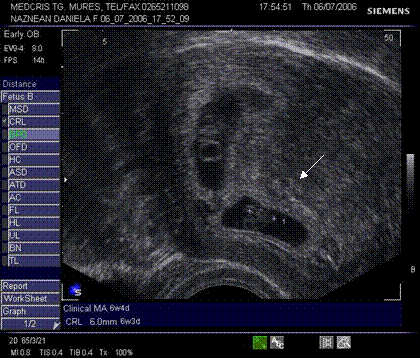

Fig nr 38. Sarcina biamniotica bichoriala 6 sapt . dupa

inseminare intrauterina cu stimulare ovariana, cele doua sageti marcheaza zona

de nidatie, respectiv placentatie, iar sacii amniotici sunt evident separati,

cu cate un embrion